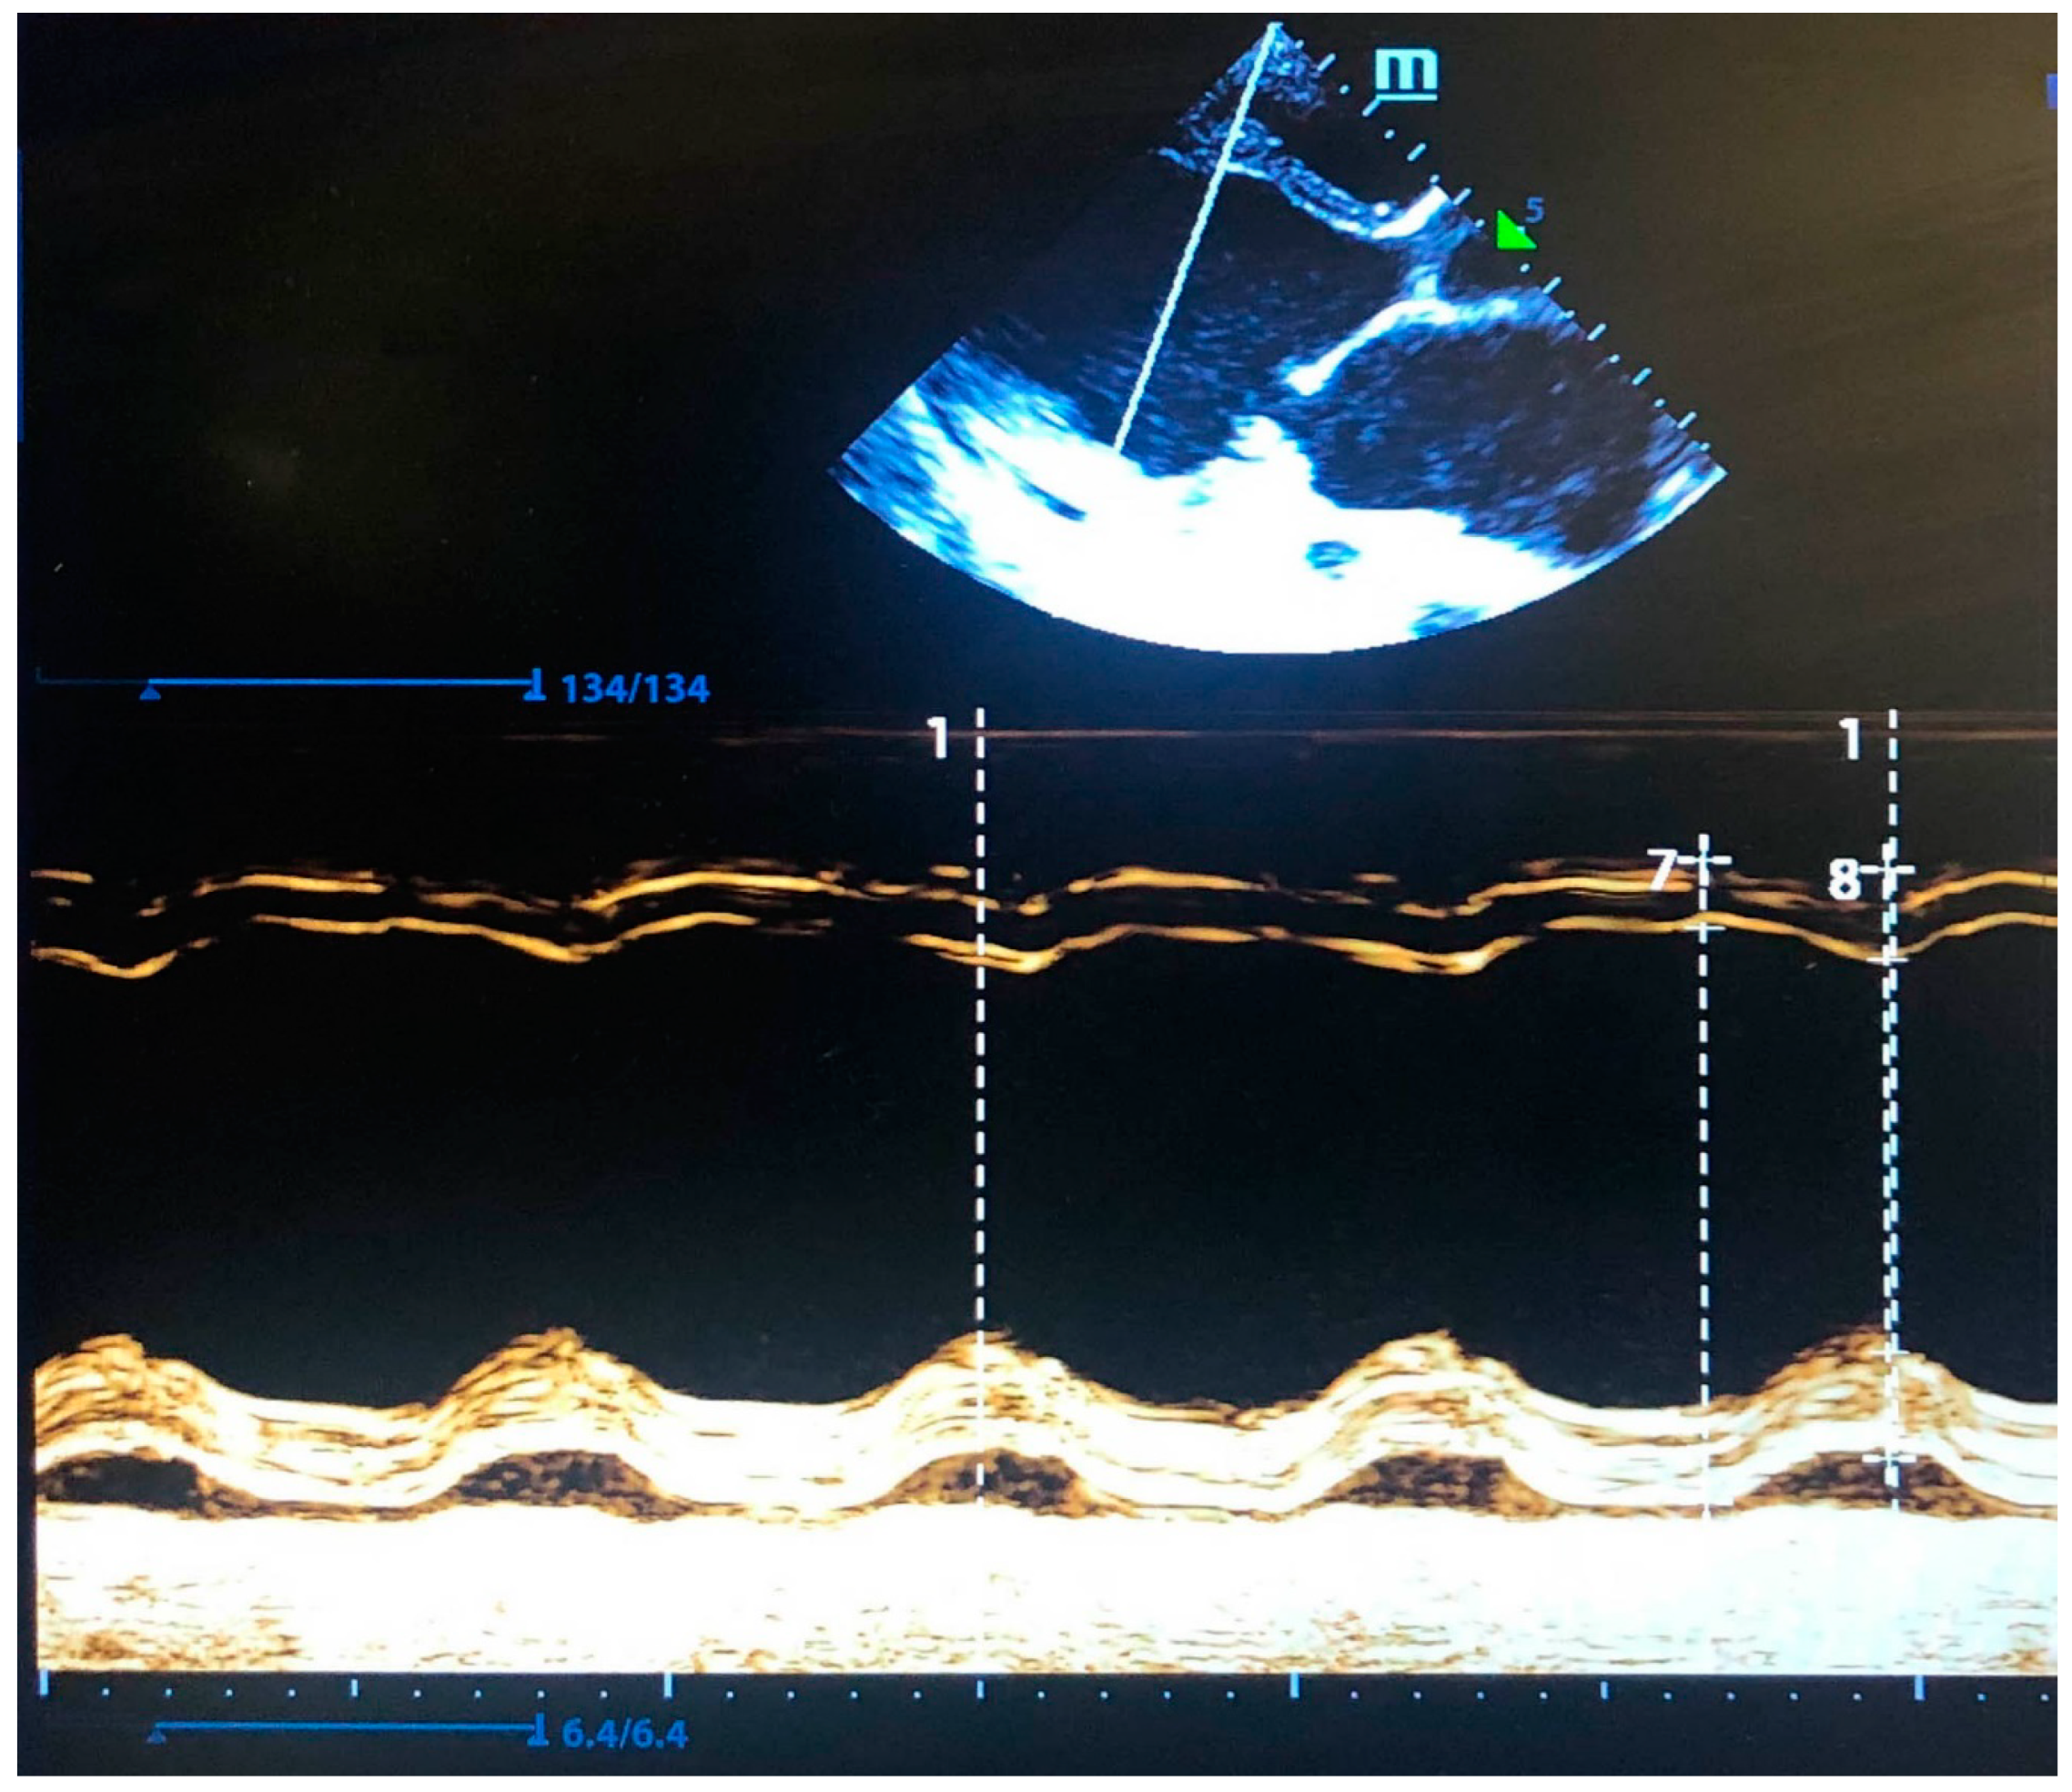

Due to RSV bronchiolitis at 3 years of life, the child required hospitalization in the intensive care unit with mechanical support. It should be noted that despite the infection, there was no deterioration in cardiac function (Figure 3). After 2 months, the boy was discharged home with a recommendation of long-term inhalation therapy.

Figure 3. Echocardiography picture of the left ventricle at the age of 3 years (M-mode): EDVT = 139.96 mL, ESVT = 73.08 mL, SV = 66.88 mL, EF = 47.79%, FS = 24.26%, HR = 82(2) Bpm. The white numbers indicate the systolic and diastolic cardiac cycle.